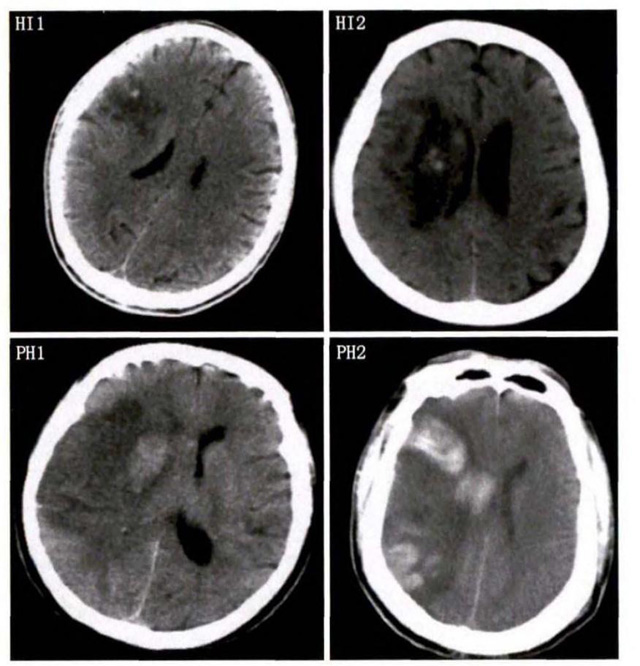

中、老年病患,有動脈粥樣硬化及高血壓病等腦卒中的危險因素,發病結合神經系統癥狀和體征,應當考慮急性腦梗死的可能。再經腦CT/MRI發現梗死灶,或排除腦出血、炎癥性疾病等,診斷即可確定。腦梗死有時頗似小量腦出血的臨床表現。腦栓塞在任何年齡都可以有發病的風險,可以在幾秒到幾分鐘達到頂峰。會有偏癱不能說話等局部神經功能損壞。栓子來源很種,可能是冠心病、心肌梗塞、心內膜炎等。合并心房纖顫,結合其他臟器官的支持診斷,CT跟磁共振都可以檢查確定栓塞位置數量還有是不是有伴發出血等問題。可以幫助診斷。

中老年有高血壓糖尿病發病病史,起病神經功能缺損癥狀,臨床表現為腔隙綜合征,即可初步診斷本病。如果CT或磁共振證實有與神經功能缺失一致的腦部腔隙病灶, 符合大腦半球或腦干深部的小穿通動脈病變,即可明確診斷。少數患者隱匿起病,無明顯臨床癥狀,在影像學檢查時發現。